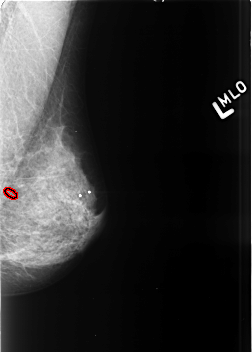

Refer to caption

Normal

Benign

· Refer to caption Malignant

Figure 4: Images of Breast Cancer Histopathology from the Mini-DDSM Dataset

4.1.2 Dataset

Our network is trained and evaluated on three main datasets: BreakHis b6 , containing 7,909 breast cancer histopathology images (2,429 benign and 5,429 malignant) at 40×, 100×, 200×, and 400× magnifications, each 700×460 pixels; Mini-DDSM b7 , a reduced version of DDSM with approximately 2,000 annotated mammography images detailing lesion locations and diagnoses; and BACH from ICIAR2018 b8 , with 400 HE-stained images in four categories (Normal, Benign, In-situ carcinoma, Invasive carcinoma), each 2048×1536 pixels. Fig. 3, 4, and 5 depict sample images from the BreakHis, Mini-DDSM, and ICIAR2018 datasets. Tables 1, 2, and 3 also present statistical data for these datasets, including sample sizes and class distributions.